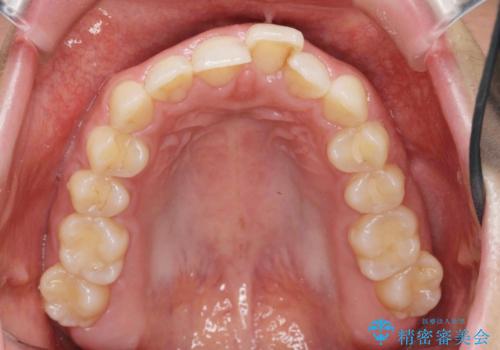

前歯のガタつきをきれいに マウスピース矯正治療

- 「前歯のガタつきをきれいにしたい。」と矯正治療を希望され来院されました。

前歯のガタつきをワイヤー部分矯正、上顎前突の咬合関係を後方移動することで理想的な咬合関係を確立します。

上顎の全体的な後方移動を実現するためにマイクロインプラントを併用したゴムかけを行ったことで理想的な咬合関係を確立することができました。